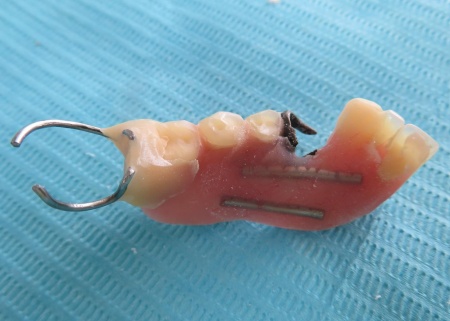

治療前

| ご相談内容 | 「入れ歯が割れてしまった」とご相談いただきました。 左下奥歯にかけるクラスプ(入れ歯を固定するための金属製の留め具)は、以前当院で修理を行っています。 |

| カウンセリング・診断結果 | 患者さんの噛み合わせは、下顎が上顎より前に出ている極端な反対咬合の状態でした。 反対咬合は入れ歯を安定させるのが難しく、噛む力が特定の部分に集中しやすいため、入れ歯の破損や変形が起こりやすいとされています。 また、残っている歯の一部には揺れがみられました。 これは、歯を支える骨(歯槽骨)が弱ってきており、歯が噛む力を十分に受け止められなくなっていることが原因です。 お持ちいただいた入れ歯は完全に割れていて、このまま使い続けるのは難しい状態でした。 ただこの段階で新しい入れ歯を作っても、ぐらついている歯が抜けてしまい、短い期間で修理や作り直しが必要になるリスクがあります。 以上のことから、まずは現在の入れ歯を修理して使えるようにしたのち、揺れている歯が自然に抜けて口腔内が落ち着くのを待ったうえで、新しい入れ歯を作製するのが適切だと診断しました。 |

| 行ったご提案・治療内容 | 診断内容をお伝えしたうえで、割れた入れ歯の修理を提案しました。 患者さんはこれまでにも同様の治療を経験されており、治療方針については十分にご理解とご納得いただいています。 まず、技工用の瞬間接着剤で割れた入れ歯を仮止めします。 これは、次の工程で正確な模型を作るための準備です。 次に、仮止めした入れ歯をお口の中に戻して型取りを行い、石こうを用いて模型を作製しました。 模型上で修理を行うことで、口の中でしっかりと合う入れ歯に仕上げることができます。 続いて、割れた部分に対して垂直に交わる向きに金属製の補強線(ワイヤー)を埋め込みました。 補強線をいれることで入れ歯のプラスチック部分にかかる力を吸収・分散できるため、割れにくい構造になります。 最後に、補強後の入れ歯を丁寧に研磨して仕上げを行い、見た目や装着感、噛み合わせに問題がないことを確認して、治療を終了しました。 |

技工用の瞬間接着剤で仮止めします。

石こうで模型を作製しました。

補強線をいれるための溝を作ります。

補強線を入れました。